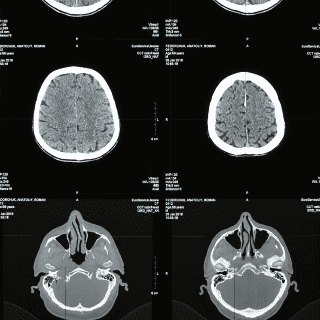

De acuerdo con Clínica Mayo, la demencia no es una enfermedad en sí misma, sino un conjunto de síntomas que afectan la memoria, el pensamiento y las habilidades sociales, provocados por diferentes condiciones médicas.

En algunos casos, estos síntomas pueden interferir de manera significativa en la vida diaria. Aunque la pérdida de memoria suele ser una de las primeras señales de advertencia, no siempre indica demencia, ya que puede tener diversas causas.